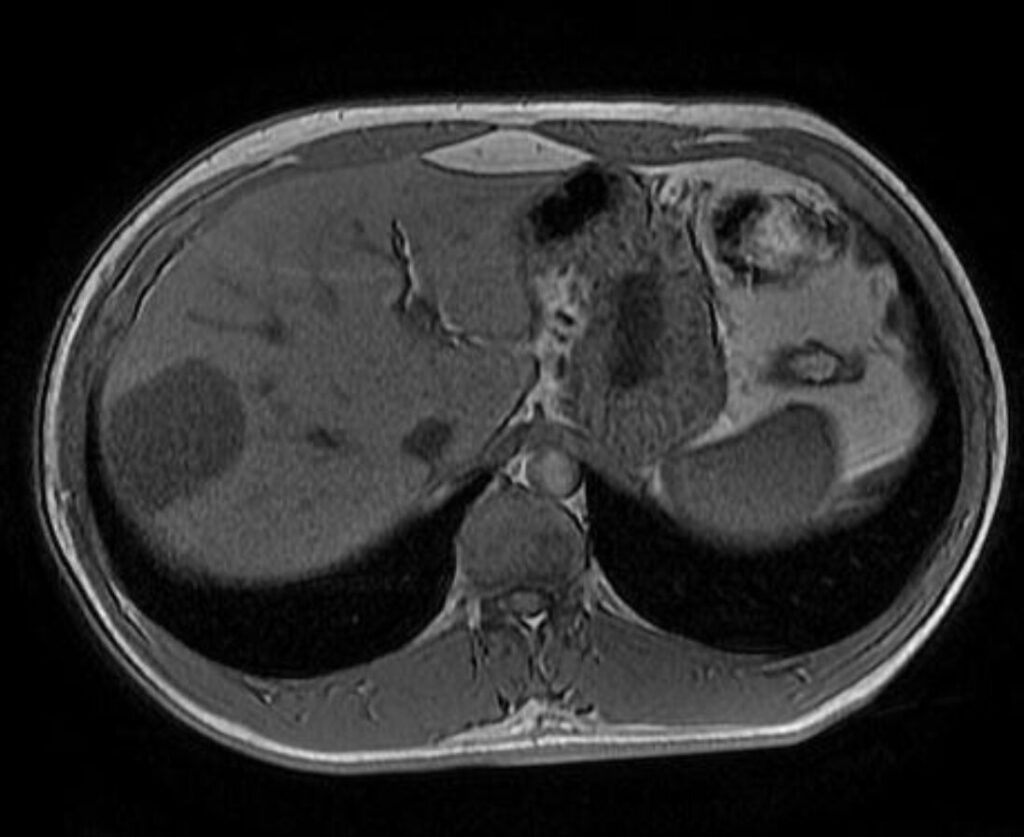

Aspetto RM

- Alterazione focale iso-ipointensa in T1, marcatamente iperintensa in T2, caratterizzata da un rapido e omogeneo enhancement in fase arteriosa senza wash-out, con ipointensità in fase epatospecifica.